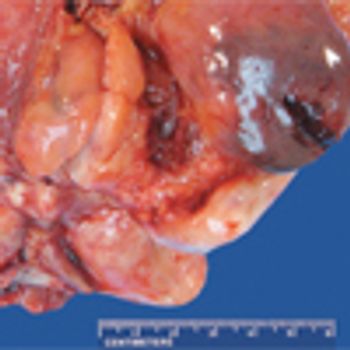

A 70-year-old man presented at our institution for a second opinion regarding diagnosis of a urinary bladder mass. He had a 3-year history of worsening urinary incontinence and urgency, for which he had undergone colonoscopy, as well as testing for prostate issues; all test results were negative.